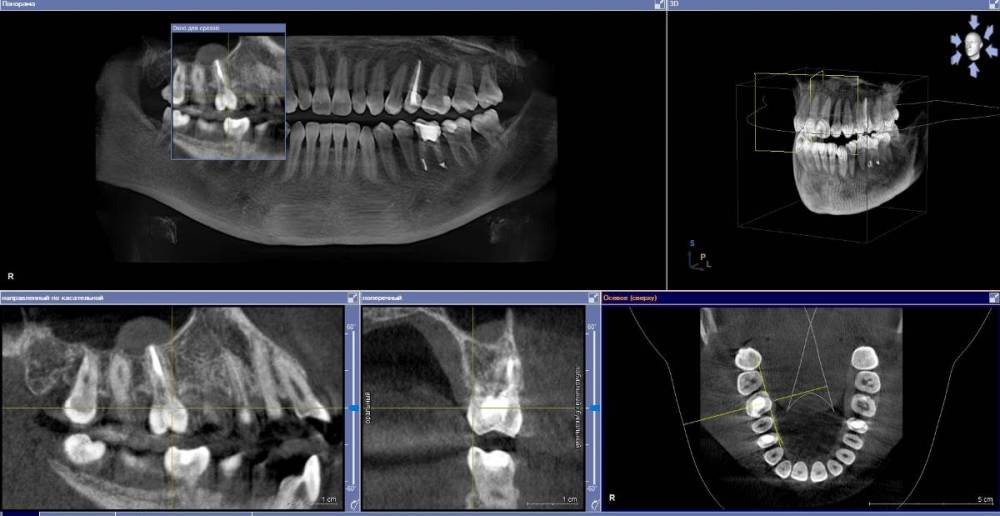

anishuma Опубликовано 1 сентября, 2021 Поделиться Опубликовано 1 сентября, 2021 (изменено) Здравствуйте, прошу помочь разобраться с моими КТ и направить для дальнейших действий. История такая: в 2018 году шестой зуб сверху справа был депульпирован. Долго сохранялись боли при нажатии, при жевании, зуб реагировал на холодной и горячее. Врач, который лечил, заверила что это постпломбировочные боли и скоро пройдет. Коронку побоялась ставить из-за этих болей. Затем примерно через год отлетел кусочек пломбы. Зуб восстановили для дальнейшей установки коронки. На данный момент есть ощутимая реакция на давление, при жевании, при чистки зубной щеткой. Зуб реагирует на холодное-горячее. Один врач сказал, что не видит показаний для перелечивания каналов. Другой врач настаивает на удалении зуба. Подскажите, пожалуйста, где истина, и возможно ли сохранить зуб. Изменено 1 сентября, 2021 пользователем anishuma Ссылка на комментарий

Bier Опубликовано 2 сентября, 2021 Поделиться Опубликовано 2 сентября, 2021 похоже что есть гранулема на корне 2 Ссылка на комментарий

St. Опубликовано 3 сентября, 2021 Поделиться Опубликовано 3 сентября, 2021 +1 к гранулеме. Я бы перелечивала каналы. Но нужно в процессе будет смотреть нет ли трещин в корне. Ссылка на комментарий